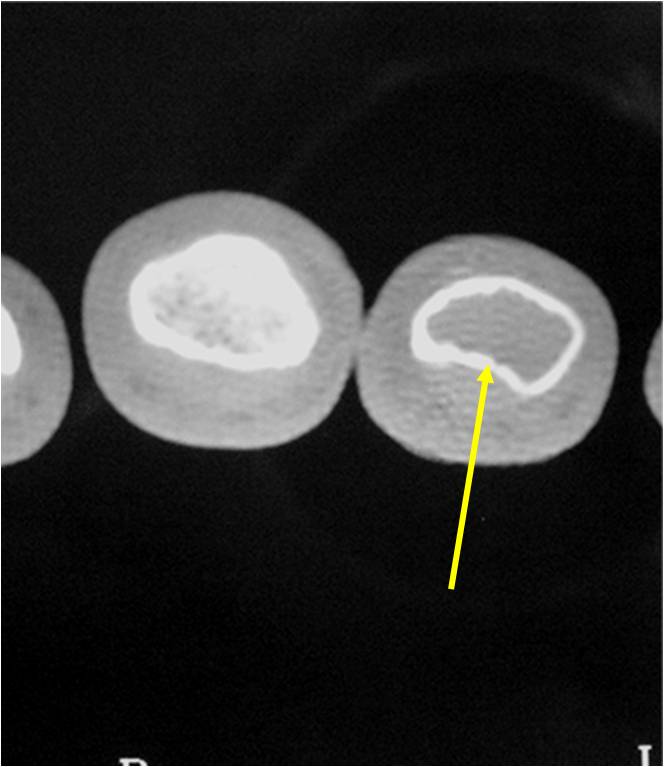

MRI:

- Lobulated margin (Lobular Growth Pattern)

- T1 Weighted Images: Intermediate Signal Intensity

- Calcifications will be low signal

- T2 Weighted Images: High Signal Intensity

- High water content shows as high signal on T2 weighted images

- Marked increased intensity long TR images

- Calcified chondroid – low intensity all sequences

- There should never be any cortical destruction nor a soft tissue component. If this exists then the tumor must be a chondrosarcoma.

- Endosteal scalloping and cortical expansion is acceptable for phalangeal tumors. In most benign long bone cartilage tumors there is minimal endosteal scalloping but there should be no cortical expansion nor thickening. There should be no cortical destruction and no soft tissue component associated with an enchondroma. Cortical destruction, periosteal thickening, cortical expansion and a soft tissue component indicates a chondrosarcoma of the long bone.